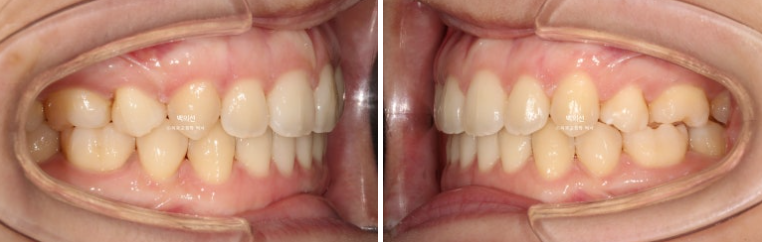

23.01~25.07

맞아진 중심선과 개선된 앞니 개방교합. 이제 면 편하게 끊어 드실 수 있겠어요.

어금니 교합이 기존 3급에서 정1급 교합관계로 바뀌었습니다.